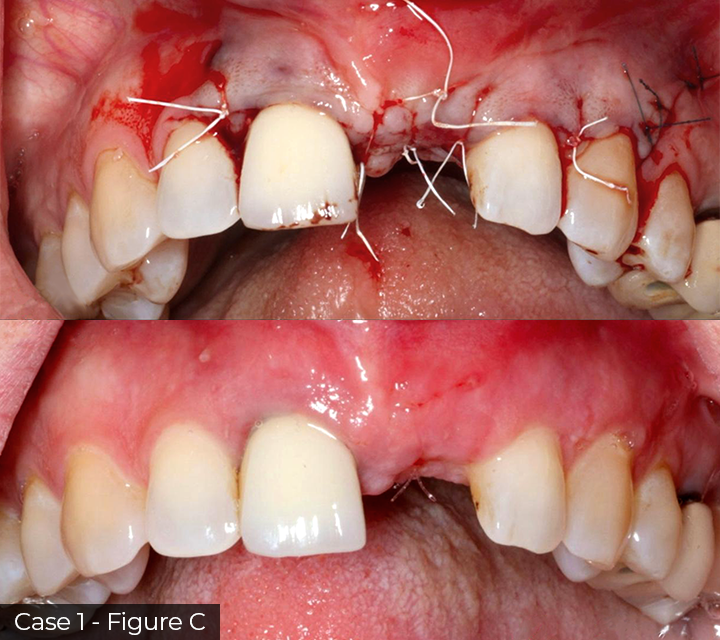

Director’s Clinical Cases

Director’s Clinical Cases